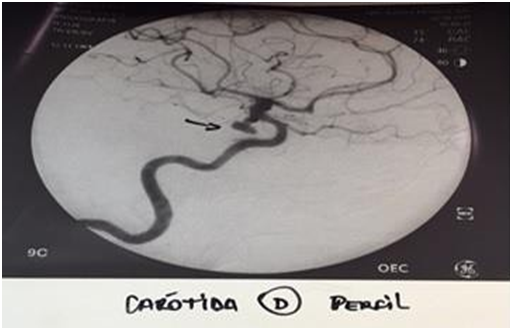

Female patient, 51 years old, brown, born in Juazeiro, Ceará. There was a month with progressive headache, pulsatile type in fronto-temporal region and right retro-ocular. In a few days, the right palpebral ptosis and hyperalgesia in V1 topography were added to the headache. Use of analgesics without clinical improvement ("the pain was so intense that she considered the possibility of suicide"). Absence of history of aneurysm and systemic diseases in the family. Deny contraceptive use. At physical examination: regular general condition, painful fascia, afebrile, atypical gait, eudychokinesis, right palpebral ptosis, as shown in Figure 1, consensual photoreagent, right mydriasis, as shown in Figure 2, hyperalgesia in V1 topography, strabismus divergent, as shown in Figure 3 & 4, and photophobia. Angiography confirmed the presence of sacculate aneurysm of the posterior communicating segment of the right internal carotid artery, as shown in Figure 5, also confirmed by magnetic resonance and magnetic resonance angiography, as shown in Figure 6 & 7. During the surgical procedure it was confirmed that the aneurysm dissected the cavernous sinus. However, it was observed that, instead of the lateral aneurysm in contact with the third cranial pair in the temporal, which is the habitual one, it made a medial orientation in contact with this in the cavernous sinus, due to the conformation of the aneurism in the form of hammer.6 This can also be justified by the fact that the posterior communicating artery in this case has no fetal pattern and the caliber of it is inferior to the posterior cerebral artery branch P1.6 In this way, it leaves the internal carotid artery in a more medial orientation.6 In the postoperative period there was an improvement in pain, but palpebral ptosis on the right, divergent strabismus, consensual photoreagent, fixed right mydriasis and photophobia persisted. Control angiography showed absence of residual aneurysm in the posterior communicating segment of the right internal carotid artery. Figure 8 shows the clipping of the region involved in the postoperative period.

Figure 5 Angiography showing aneurysm in the right internal carotid artery.